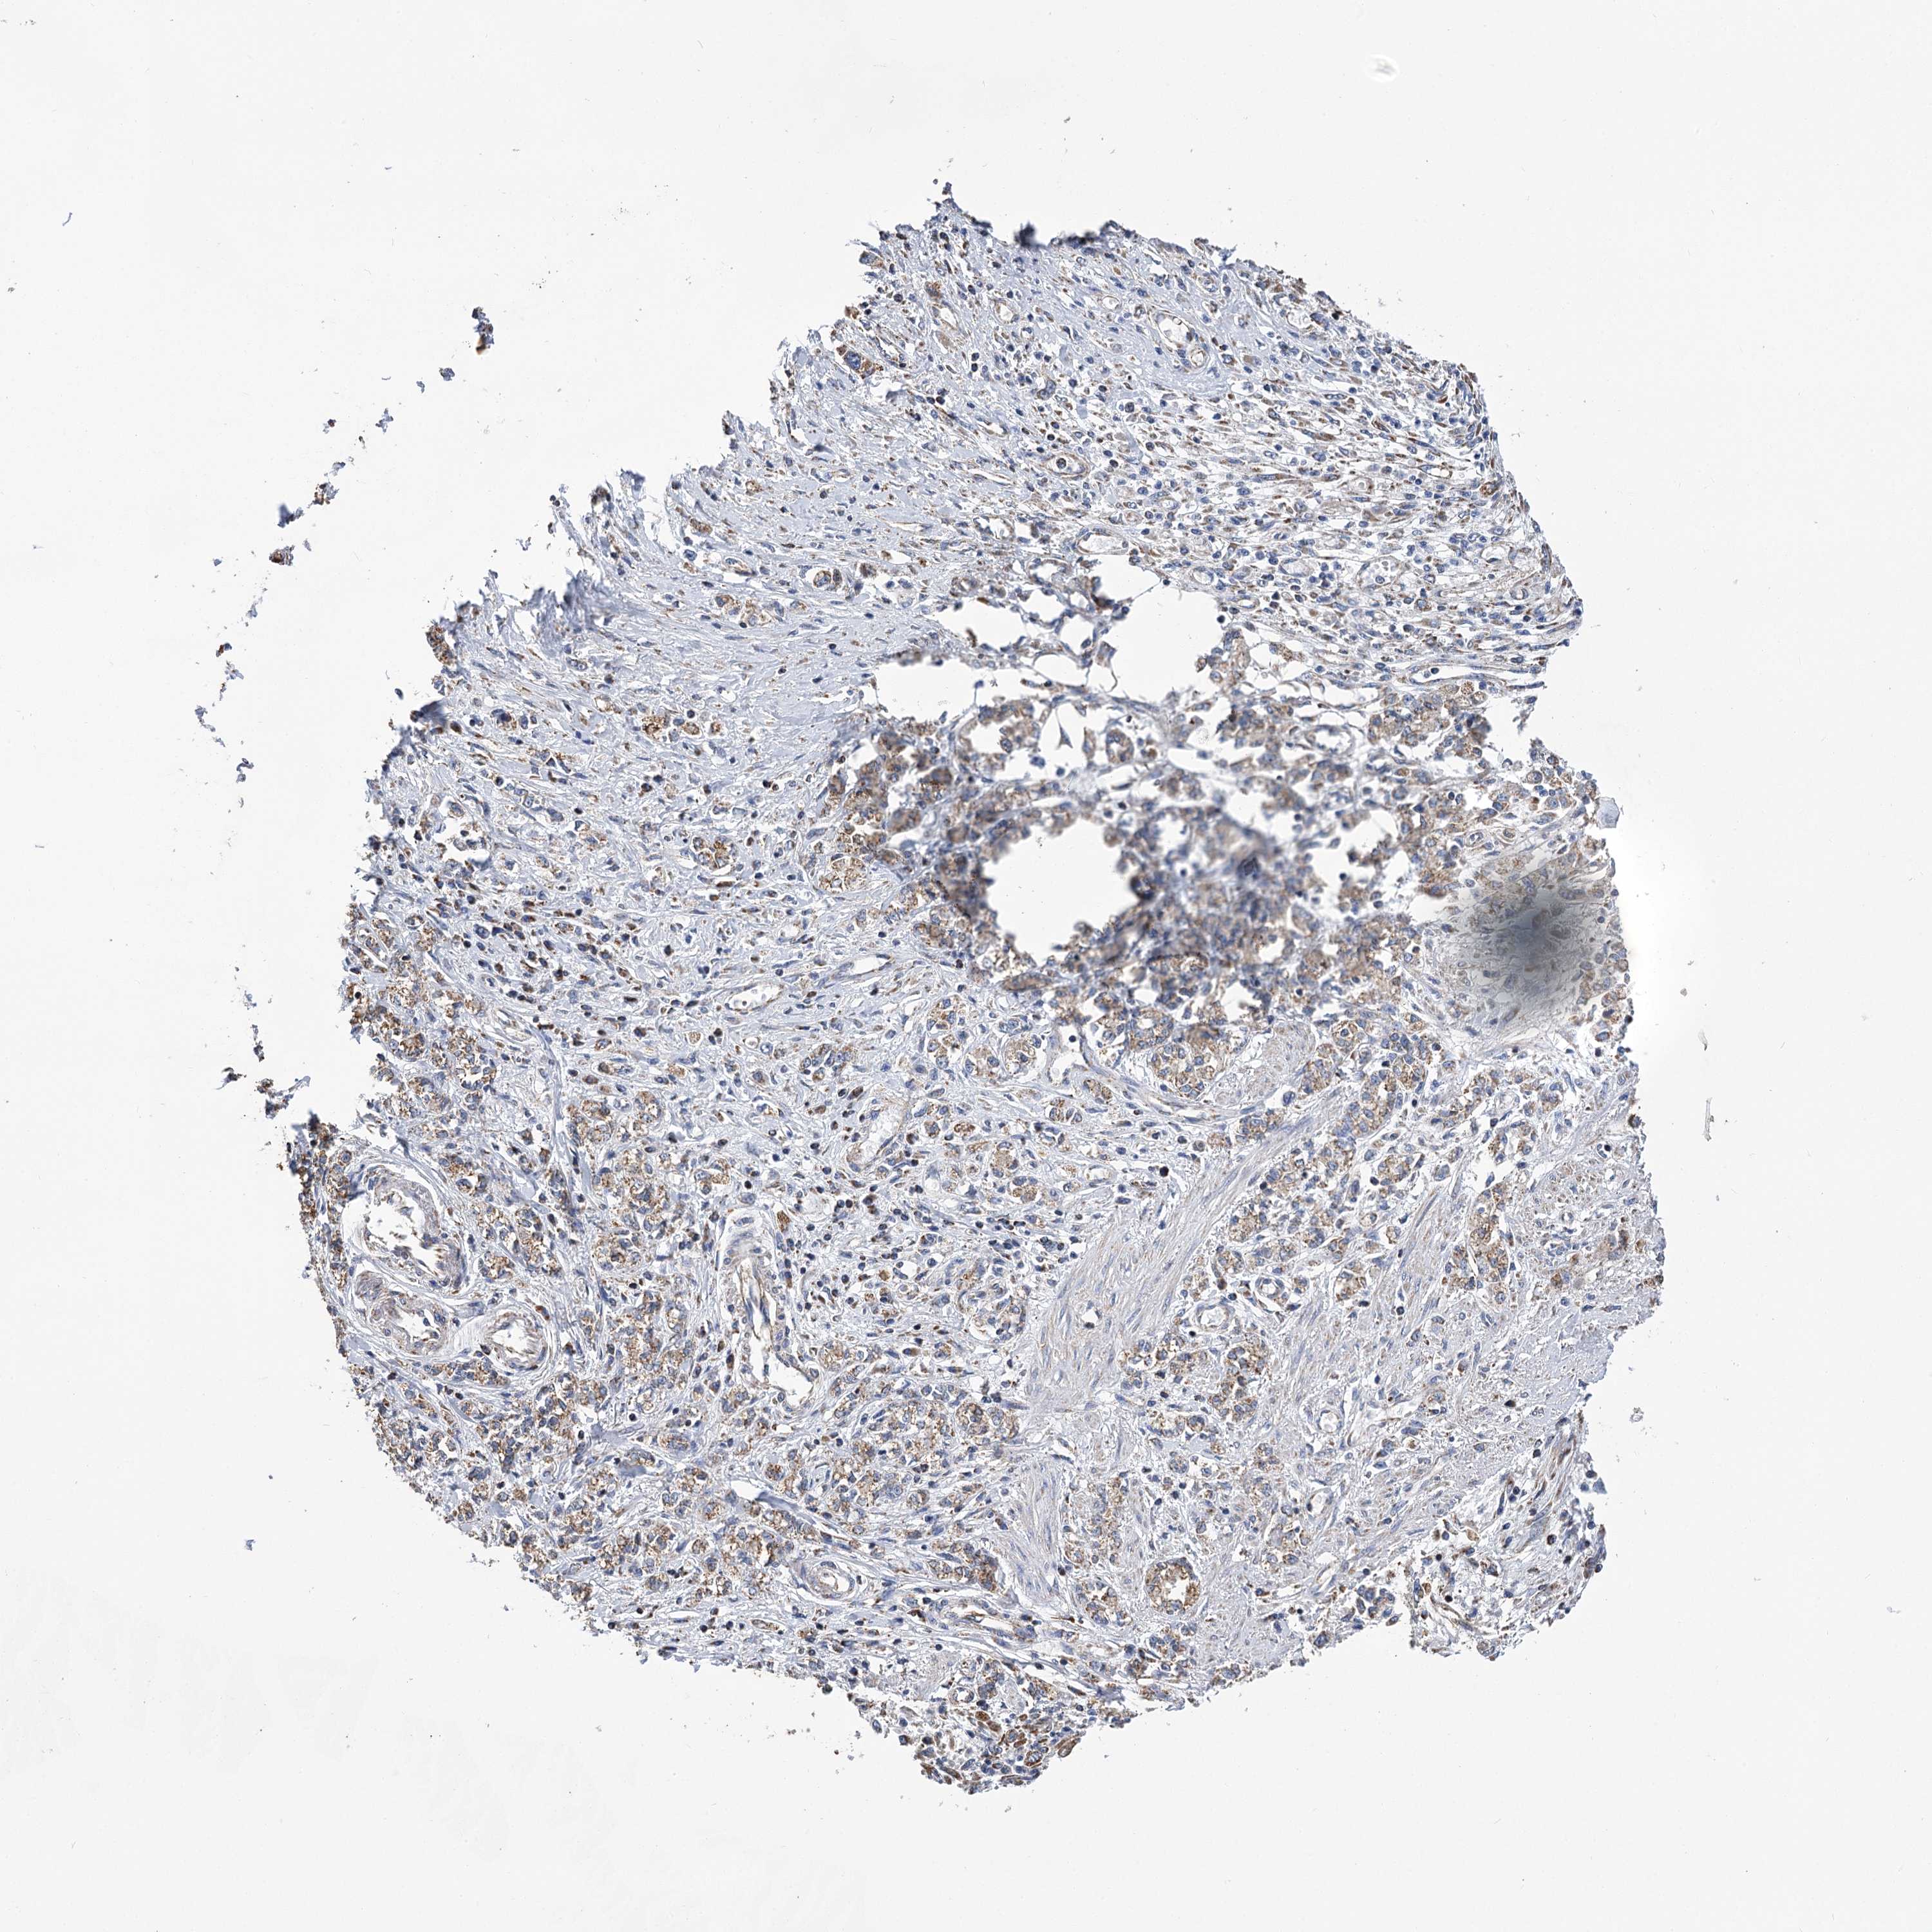

STOMACH CANCER - Protein expressioni

A mouse-over function shows sample information and annotation data. Click on an image to view it in a full screen mode. Samples can be filtered based on level of antibody staining by selecting one or several of the following categories: high, medium, low and not detected. The assay and annotation is described here.

Note that samples used for immunohistochemistry by the Human Protein Atlas do not correspond to samples in the TCGA dataset.

Antibody stainingi

Antibody staining in the annotated cell types in the current human tissue is reported as not detected, low, medium, or high, based on conventional immunohistochemistry profiling in selected tissues. This score is based on the combination of the staining intensity and fraction of stained cells.

Each image is clickable and will lead to virtual microscopy that enables deeper exploration of all samples and also displays staining intensity scores, fraction scores and subcellular localization as well as patient and tissue information for each sample.

Antibody HPA038668

Antibody HPA038669

Staining

High

Medium

Low

Not detected

Intensity

Strong

Moderate

Weak

Negative

Quantity

>75%

75%-25%

<25%

None

Location

Nuclear

Cytoplasmic/membranous

Cytoplasmic/membranous,nuclear

Adenocarcinoma, NOS

Adenocarcinoma, High grade